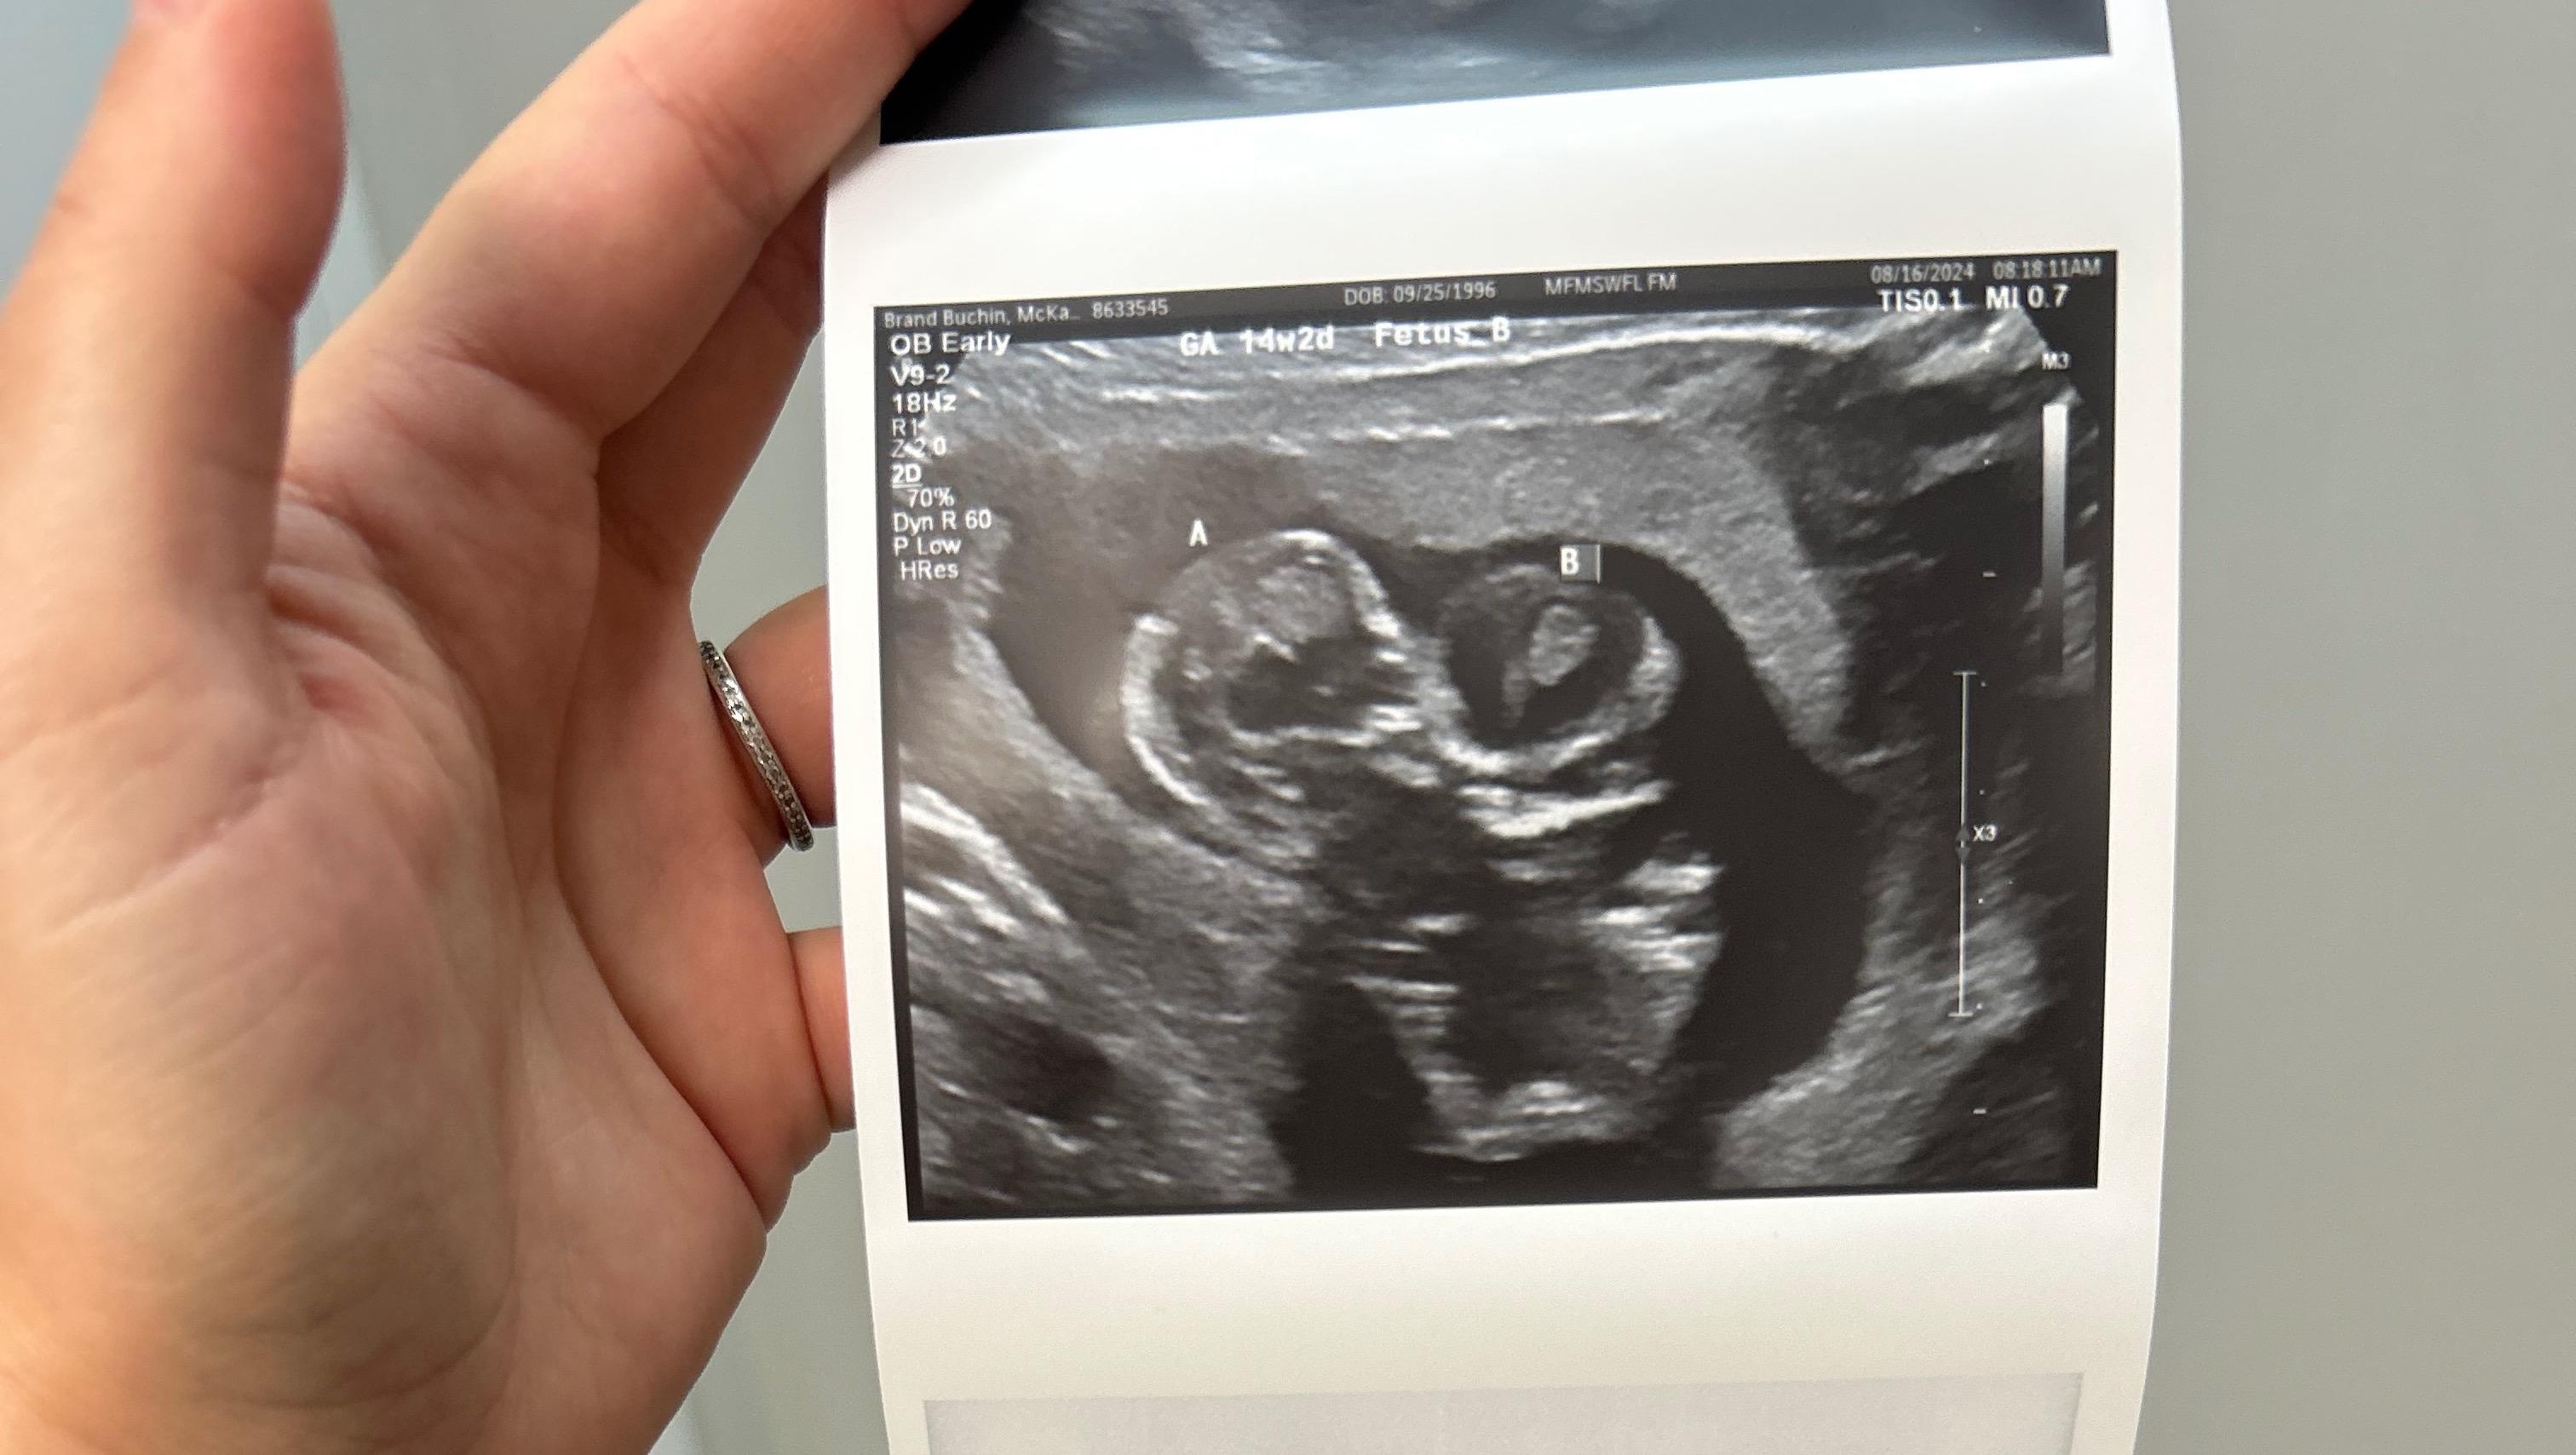

This week, we found out our baby boy was actually a twin. A day later, we found out they shared one heart and were told that there was nothing we could do but to end the pregnancy. Because Florida has a 6-week law in place, nothing is covered by insurance and we had to pay for specialists and the procedure out of pocket. On top of that, having to drive to the other coast, get a hotel, & take time off work. I hate asking for help but real life doesn’t stop even when heartbroken.